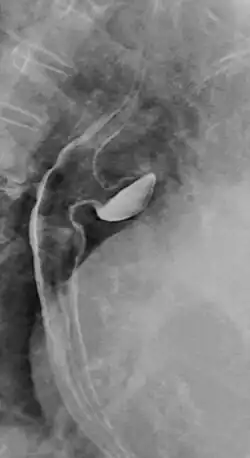

Ösophagusdivertikel

Das Ösophagusdivertikel und der Ösophaguspouch sind Ausstülpungen bzw. Erweiterungen (Divertikel) der Speiseröhre, die sich in unterschiedlichen Höhen derselben finden, unterschiedliche Ursachen und einen unterschiedlichen Krankheitswert haben. Man unterscheidet

- Killian-Jamieson-Divertikel

- Zervikale ösophageale Pouches

- Traktions- und Pulsionsdivertikel des mittleren Ösophagus

- Barsony-Pseudodivertikel

- echte epiphrenische Divertikel